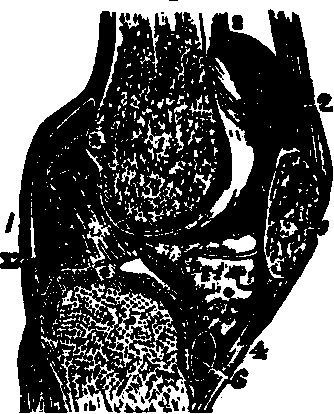

Fig.

17. Anatomy of a joint, 1, 1. Bones of a joint. 2, 2. Cartilage. 3, 3, 3, 3. Synovial

membrane.

Fig. 18. Anatomy of knee joint. 1. Lower

end of thigh-bone. 3. Knee-pan. 2, 4 Ligaments of the

knee-pan. 5. Upper end of the tibia, or shin-bone. 6, 12.

Cartilages.